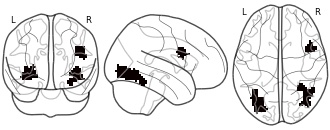

"name": "Multi_VBMsmaller_fMRIdecreased",

"description": "Multi-modal analysis in BPD. Brain regions exhibiting smaller gray matter and decreased activation during emotion processing in BPD compared to healthy controls. Note: Results were thresholded at p<.0025. Note2: Results were updated (see Erratum for this publication).",